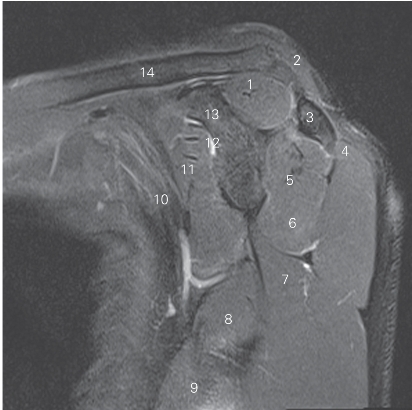

图4-21 经肩锁关节的矢状断层MR T2WI FS

1 锁骨 clavicle 2 肩锁关节 acromioclavicular joint

3 肩峰 acromion 4 冈下肌 infraspinatus

5 肱骨头 head of humerus 6 三角肌 deltoid

7 小圆肌 teres minor

8 腋神经及旋肱后动脉 axillary nerve and posterior humeral circumflex artery

9 肱三头肌 triceps brachii 10 大圆肌 teres major

11 胸大肌 pectoralis major 12 喙肱肌 coracobrachialis

13 肩胛下肌 subscapularis 14 喙突 coracoid process

15 肩袖间隙 rotator interval 16 冈上肌 supraspinatus

17 喙肩韧带 coracoacromial ligament